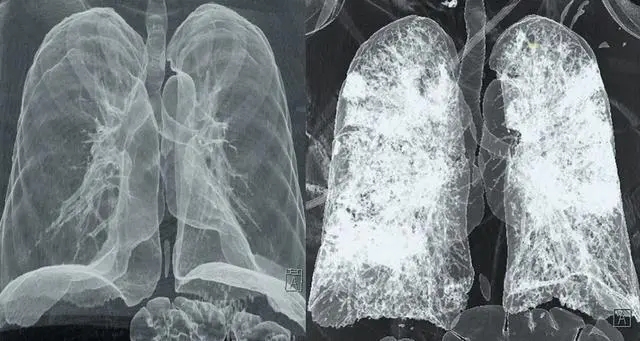

完全失去弹性的肺

干硬得像丝瓜筋

肺泡结构变硬、扩张变得费力

氧气、二氧化碳交换出现困难

这就是肺纤维化

肺纤维化属于呼吸系统疾病中的难治病,之所以说是难治病,主要是因为它是一种不可逆的慢性呼吸系统疾病,早期的时候肺泡出现炎症,反复的炎症刺激导致脏器自我修复次数过多从而修复异常。

这种异常的修复会从根本上破坏脏器的正常生理结构从而导致器官功能的逐渐衰竭,肺纤维化的患者最终因为呼吸衰竭而亡。